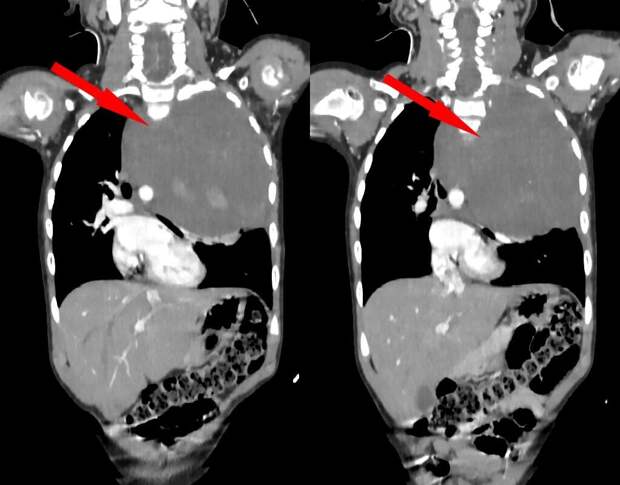

Родители показали дочь врачам, когда заметили у нее небольшую припухлость в области шеи. Специалисты по месту жительства выявили огромное новообразование размером со страусиное яйцо, которое сдавливало сердце и легкое.

Сквозь ткань опухоли проходили крупные сосуды: "позвоночная артерия, питающая головной мозг, и подключичная артерия с ее ветвями, питающая левую руку". После телемедицинской консультации ребенка направили в Москву.Столичные специалисты провели биопсию образования и установили, что оно доброкачественное. Тем не менее медики решили удалить опухоль, поскольку она "могла содержать злокачественные оттенки".